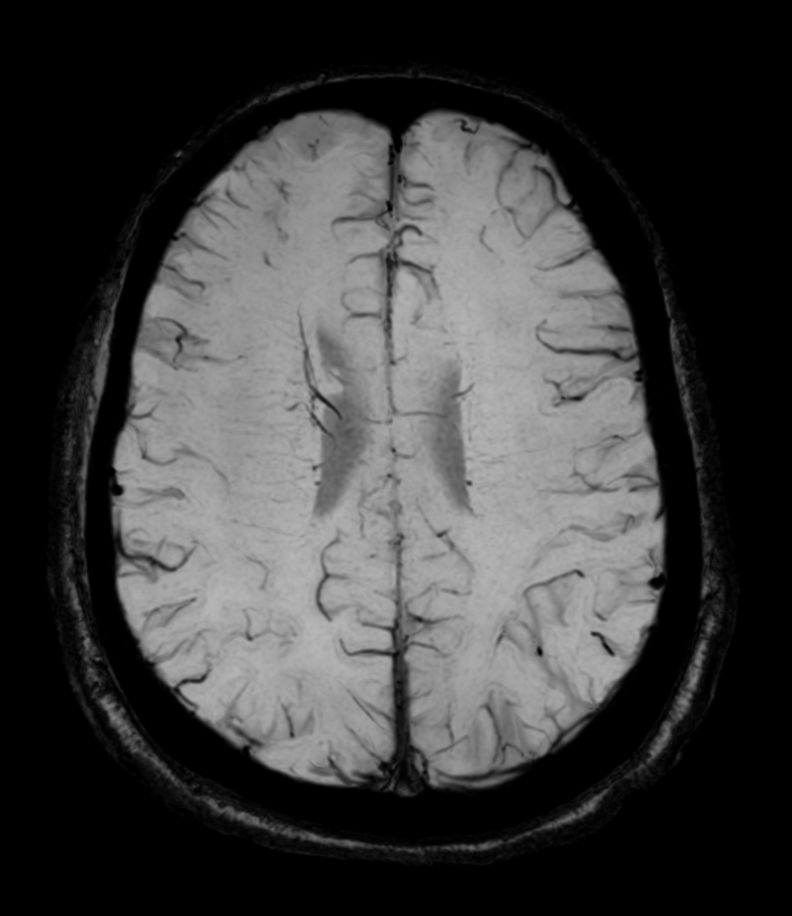

Axial SWIp